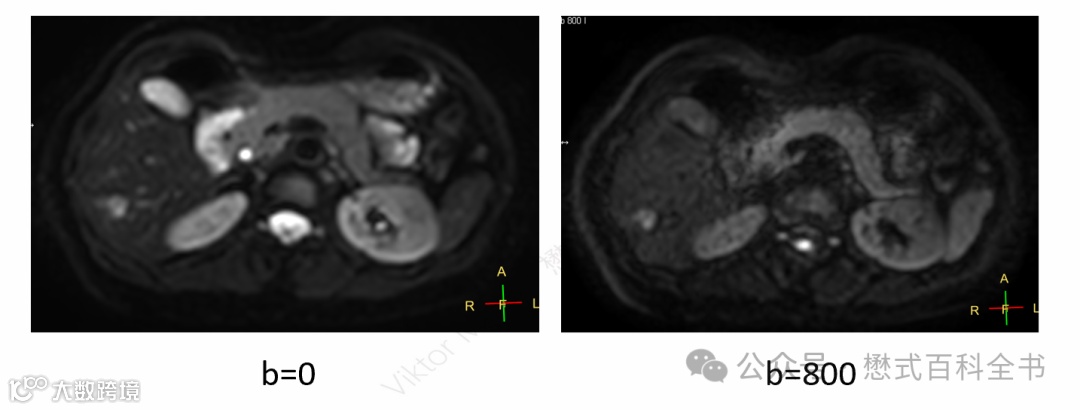

对于头颅来讲,常规的DWI一般扫描两个b值,b=0和b=1000。而对于腹部或者前列腺来讲则不同。

图8:肝脏扫描DWI:b=0和b=800(屏气扫描,19s)

不仅不会省略T2WI,有时候还会增加一个低b值的DWI图像。这个低b值不是b=0,而是b=20或50。

图9:T2WI-fs(左)和b=8的低b值DWI图像(右)

上图可以发现,常规的肝脏T2WI-fs,虽然图像信噪比高,空间分辨率也不错,但是肝脏的脉管系统是高信号。而采用了低b值的DWI,抑制了肝脏内脉管信号,对于一些小病变的检出就更敏感了。